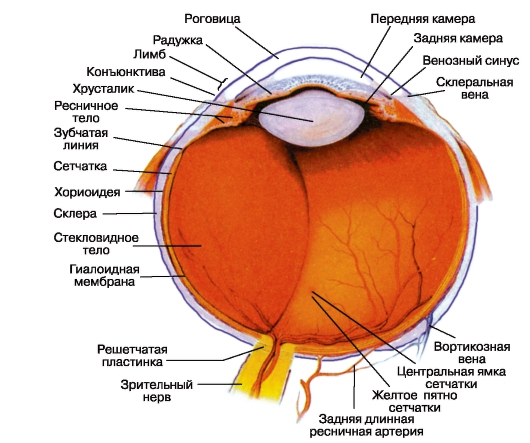

КТ-графики и изображение строения глаза